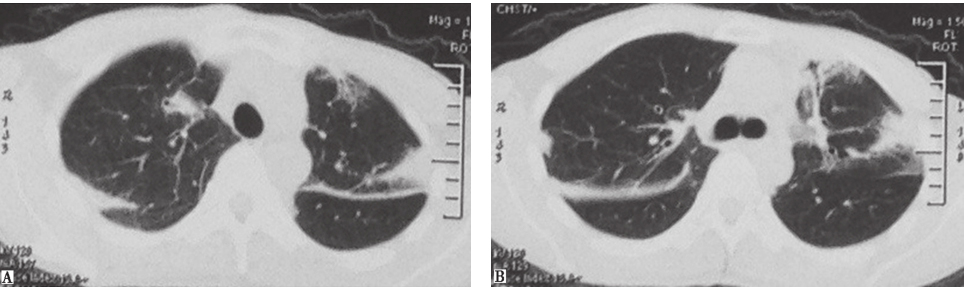

2013年1月9日病理检查结果显示,活检肺组织中见肺间质炎,淋巴细胞、浆细胞浸润,小气道和肺泡腔内局灶性息肉样纤维增生,局部淋巴滤泡形成,未见结核病变(图3)。

图3肺组织病理表现(HE染色,200×)